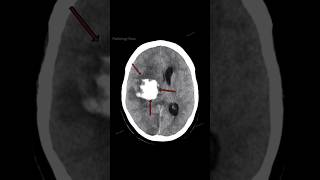

Patient With Headache, Vomiting, Confusion, &...

5.425

0:23